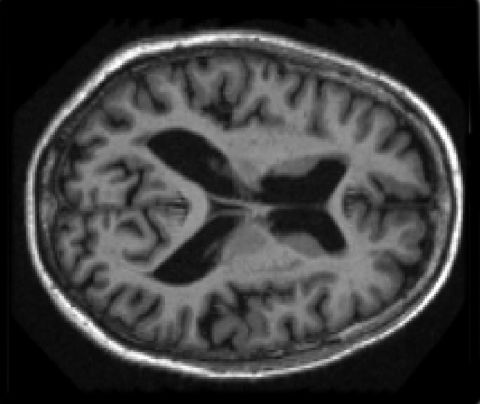

Pruebas médicas comunes, como resonancias magnéticas o tomografías computarizadas, son sólo algunos ejemplos de lo que la tecnología, y en particular las técnicas de imagen médica, aportan diariamente al ámbito sanitario. El desarrollo de estas herramientas de diagnóstico ha facilitado a los profesionales de la salud información muy valiosa en forma de datos, que deben ser procesados de la manera más eficiente posible para permitir una visualización óptima de los resultados en tiempo real.

El procesado de imagen en 2D y 3D ha resultado clave en el avance de la medicina moderna, pero su complejidad hace imprescindible el desarrollo de estrategias que permitan afrontar con garantías muchos de los retos planteados en la actualidad, como la cirugía mínimamente invasiva o los sistemas de ayuda al diagnóstico a través de la imagen; a día de hoy, el principal problema con el que cuentan estos sistemas es que están basados en algoritmos muy costosos a nivel computacional, por lo que en muchos casos su utilización en tiempo real resulta inviable.

El trabajo se ha centrado en las tareas de segmentación (usada, por ejemplo, para la identificación de órganos y tejidos o la detección de nódulos cancerígenos) y visualización, con el objetivo de que los especialistas puedan consultar los diferentes tipos de imagen médica sin esperas. En el primer caso, la tesis ha demostrado que es posible multiplicar la eficiencia del proceso por más de 50, mientras que las tareas de visualización aumentan su eficiencia entre 5 y 12 veces.